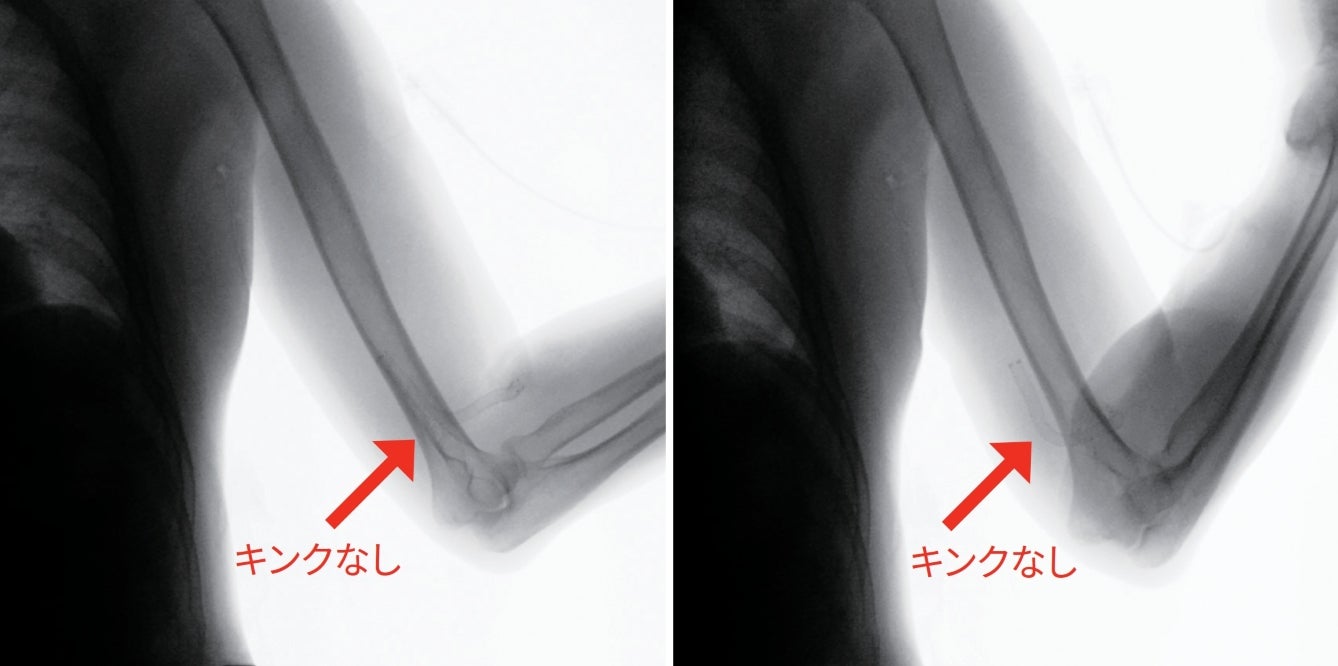

本症例は肘をまたいでデバイスを留置したが、図3のように屈曲させた状態の透視画像において、ステントグラフトのキンクは認めなかった。ステントグラフト内挿術後のキンクや破断といったトラブルも認めておらず、本稿の脱稿時点(2021年9月17日時点)では問題なく経過している。